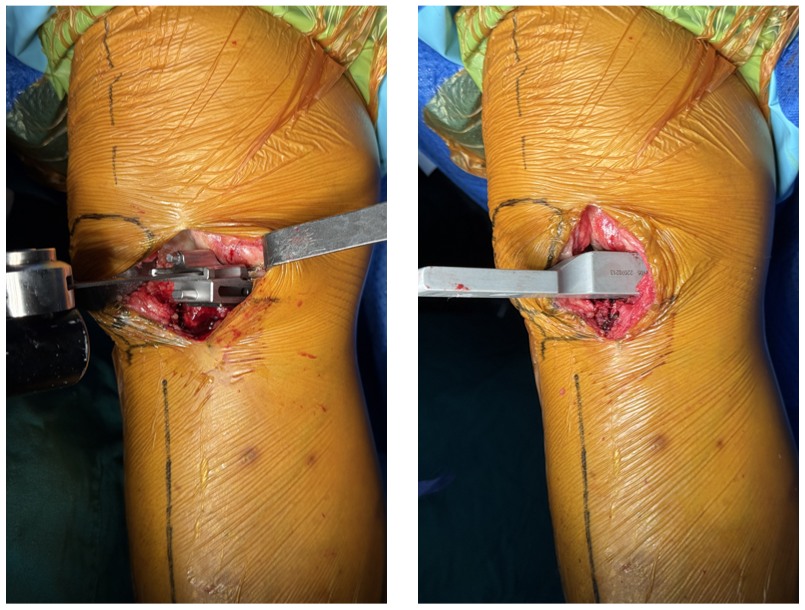

3、安放置胫骨截骨导向器

-

截骨导向器导杆的远端对准踝穴中央,踝轭指向第二趾,导杆与胫骨前缘平行(冠状面);

调节截骨导向器导杆远端,使其距离皮缘2cm,与胫骨前缘平行(失状面)。

4、胫骨近端垂直截骨

沿着已标记的纵线做垂直截骨,先锯透前侧皮质,然后放平锯片,再锯透后侧皮质;

宽度:尽可能宽,以不跨过胫骨内侧棘突顶点,不损伤ACL纤维束为原则;

方向:锯片方向与胫骨矢状轴剖面一致,与胫骨截骨导块前面垂直。